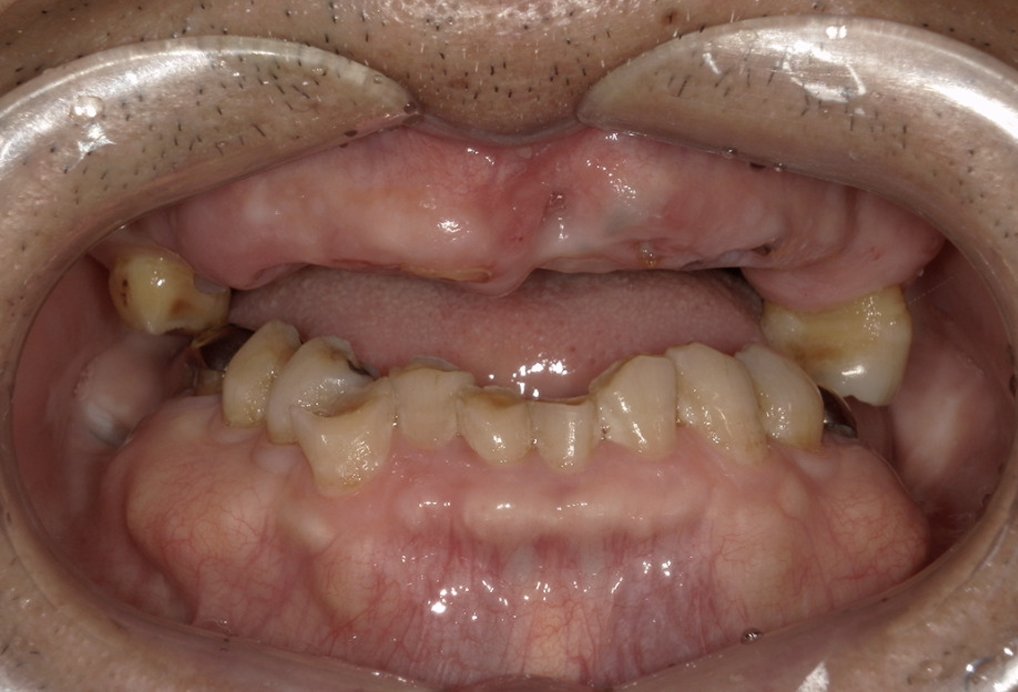

| 主訴 | 全体的にきれいにしたい |

|---|---|

| 治療内容 | 午前中に上下顎共に重度の歯周病、虫歯のため全ての歯を抜歯させていただき下顎はインプラントの土台を3本埋入し歯型を取り午後に上部構造(下顎全ての歯)を装着、上顎は一度総入れ歯を装着させていただきました。 治療が1日で完了しその日のうちに噛めるようになります。 |

| 治療期間 | 2回(1回目に資料取りをさせていただき2回目に下記の全ての治療をさせていただきました。) |

| 治療費 | 250万円 |

| 治療 リスク | 抜歯した部位などに関しては当日痛みが出ますので痛み止めなどを処方させていただきます |